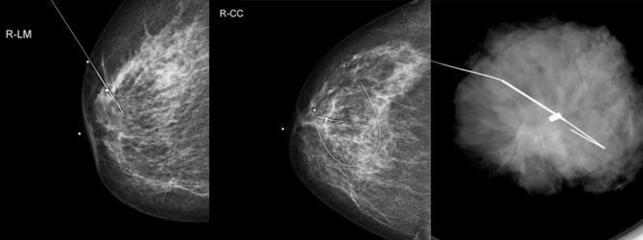

Meme ultrasonu veya mamografi ile saptanan derin yerleşimli ya da küçük boyutlu kanser açısından şüpheli özellikte olan kitlelerin cerrahi olarak çıkarılmasına yardımcı olmak için bu işlem yapılır. Ayrıca mamografide sadece patolojik (yani kanser açısından riskli olan mikrokalsifikasyon) kireçlenmeler görülen ancak henüz bir kitle oluşumuna yol açmayan çok çok erken dönemde kanser açısından şüpheli meme alanlarının çıkarılmasına da yardımcı olmak için de yapılır. Bu işlemde özel işaretleme telleri ya da coiller kullanılır. Görüntüleme eşliğinde bu teller olası kitlelerin hemen yanına konulur. Bu teller ucundaki çengel sayesinde dokuda sabit kalırlar ve yer değiştirmezler. Tel ile işaretlemeden sonra hasta operasyona gönderilir.